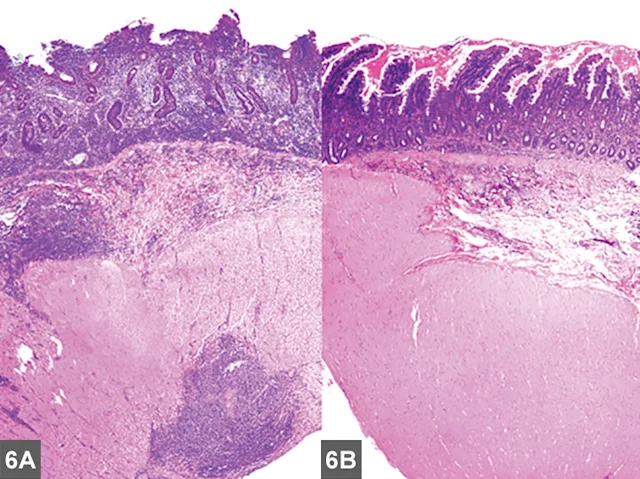

FIGURE 2A

Cranial mediastinal mass in a cat. Note the increased opacity of the entire cranial mediastinum with border effacement of the cranial margin of the heart and dorsal deviation of the trachea in the lateral view.

Mediastinal

• Typically localized form of LSA involves infiltration of the thymus and/or cranial mediastinal and sternal lymph nodes with intermediate to large neoplastic lymphocytes with signs related to the intrathoracic mass effect and secondary pleural effusion (Figure 2).